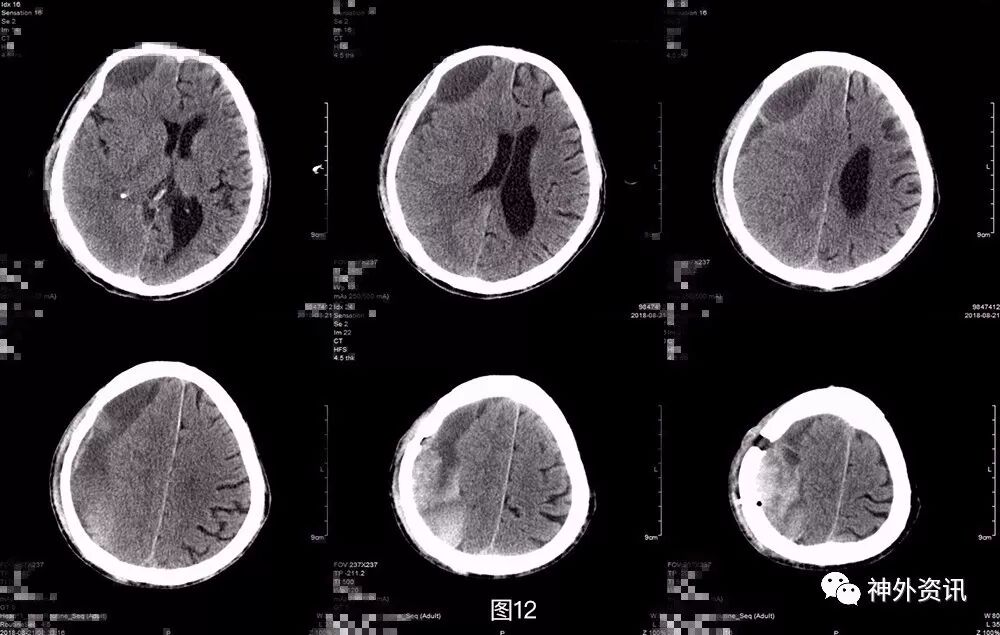

第三次术后第5天再次复查头颅CT,显示局部积气比前片吸收,但积血积液仍较明显(图9)。考虑患者神志及肢体肌力基本同前,继续予以药物保守治疗。之后患者逐渐神志转清,左侧肢体肌力好转至3-4级,期间复查头颅CT(图10)提示局部积血密度逐渐下降,提示血肿液化可能,于术后半月稳定后转康复治疗,定期复查头颅CT。

图9. 第三次术后第5天头颅CT,显示局部积气比前片吸收,但积血积液仍较明显。

图10. 第三次术后第10天,局部积血密度逐渐下降,提示血肿液化可能。

出院后患者分别于术后3周,术后5周复查头颅CT,提示血肿密度较前持续下降,中线偏移好转,占位效应较前有所缓解(图11)。

图11. 第三次术后3周,术后5周头颅CT,提示血肿密度较前持续下降,中线偏移好转,占位效应较前有所缓解。